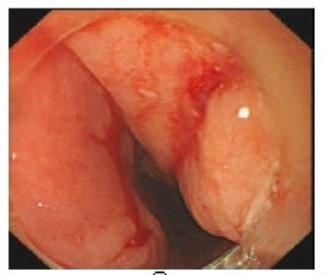

这个案例,教会了我在异物取出术中如何避免严重并发症的发生

作为一名消化科医生,夜班总是会遇到吃下各种各样东西的人前来取异物,比如鱼刺、硬币、纽扣、别针、小刀、筷子、打火机、电池等,种类各异。 记得一次普通的夜班,急诊入院一个老年女性,以...